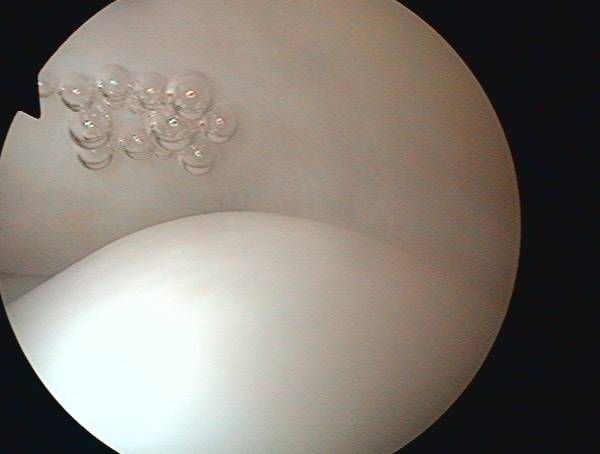

Der Eingriff erfolgt minimal-invasiv (arthroskopisch) Zunächst werden entzündliche Veränderungen entfernt und der eingeengte Knochenkanal zum späteren Schutz der Sehne erweitert. Im Anschluß daran wird die gerissene Sehne repariert (Rotatorenmanschettennaht, Sehnennaht, Rotatorenmanschettenrekonstruktion). Bei größeren Defekten erfolgt dies über einen zusätzlichen kleinen Hautschnitt.

oben: intakte Rotatorenmanschette, unten: gesunder Knorpel des Oberarmkopfes